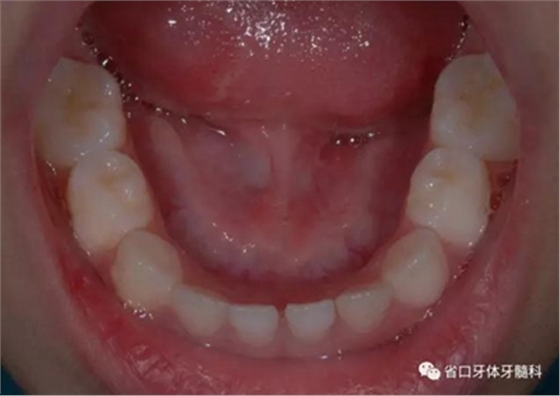

圖4 正面牙相(2015年1月)

圖11 局部牙性前牙反合可使用頜墊舌簧糾正